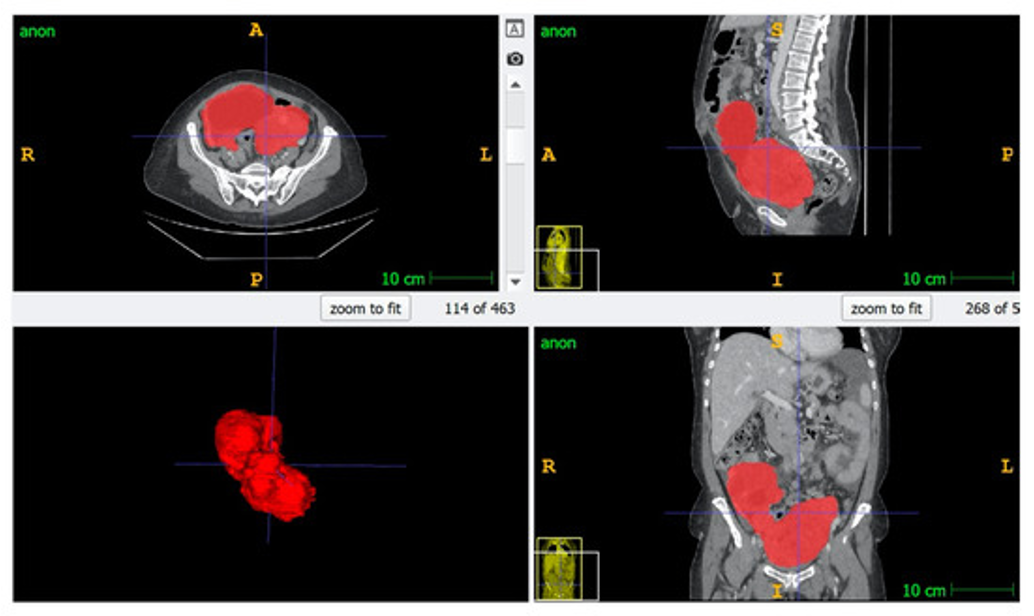

At the PINKCC Lab, our research pushes the boundaries of cross-sectional oncologic imaging to transform how cancer is detected, characterized, and treated. In partnership with Siemens Healthineers, we are developing next-generation MRI sequences that go beyond anatomy to capture tumor biology in vivo—including hypoxia and pH-sensitive CEST imaging (Chemical Exchange Saturation Transfer), which detects subtle proton exchanges between metabolites and water to map tissue acidity as a biomarker of aggressiveness. We also advance IVIM (Intravoxel Incoherent Motion)–derived parameters, separating true diffusion from microvascular perfusion, to non-invasively monitor treatment response and personalize therapy early in the course of care. Complementing this physiological imaging, our team designs AI-driven segmentation algorithms that precisely delineate tumors and peritoneal disease, providing surgeons with actionable 3D roadmaps to improve resectability, reduce morbidity, and ultimately elevate patient outcomes. Together, these innovations redefine medical imaging as a powerful decision-making tool—not just to see cancer, but to understand it.

At the PINKCC Lab, we transform medical images into quantitative biomarkers that reveal tumor biology beyond what the human eye can see. Using high-quality cross-sectional imaging and precise manual and AI-based segmentation, we extract thousands of radiomic features describing tumor shape, texture, heterogeneity, and microenvironment. These data are then integrated with clinical, pathological, and genomic information to develop predictive models that can anticipate treatment response, assess resectability, and support truly personalized cancer care. Our radiomics program is applied at scale across ovarian, rectal, and peritoneal disease, with large curated cohorts and external validation to ensure robustness and clinical translation.

Following this initial “pre-qualification” phase, the final phase was launched in partnership with Scaleway, the European cloud provider and subsidiary of the Iliad group. Overall, participants developed and trained their models on more than 300 ovarian CT scans, collected, anonymized, structured, and annotated by the teams at the Montpellier Cancer Institute.